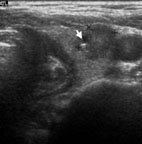

蔡先生因在左頸有腫塊而到耳鼻喉科門診就診(圖5),頭頸部的局部檢查除了左頸有界限糢糊不清的腫塊外其它包括鼻咽部(圖6)並沒有明顯異常,以頭頸部超音波檢查發現淋巴結預測值高於7分(圖7),超音波導引下細針穿刺細胞學檢查懷疑是轉移性鼻咽癌後,接受內視鏡鼻咽部切片證實為鼻咽癌。由於蔡先生超音波導引下細針穿刺細胞學檢查,避免了過去常見的頸部腫塊的切片手術。蔡先生接受放射腺治療後,腫塊即消失,因此可見頸部腫塊的切片手術對於鼻咽癌的診斷治療是不必要的。

圖7. 頭頸部軟組織超音波檢查,惡性淋巴結預測值高於7分,超音波導引下細針穿刺懷疑是轉移性鼻咽癌,後由鼻咽部切片證實為鼻咽癌

圖9. 楊小姐因為頸部酸痛到耳鼻喉科門診求診,頭頸部的局部檢查並沒有明顯異常,頭頸部超音波檢查發現右側甲狀腺結節,超音波影像發現是實心的腫瘤且有微小鈣化(箭頭所指處),超音波導引下細針穿刺細胞學檢查發現甲狀腺乳突。